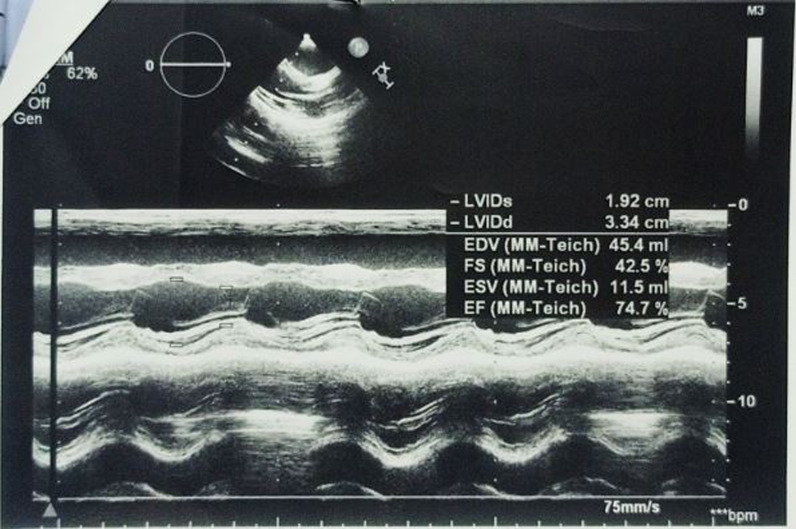

The investigations started with laboratory tests (Table 1). Complete blood count (CBC) and blood smear showed pancytopenia. However, the bone marrow biopsy was normal. Esophagoscopy used to be done every 3 months for the past year. In the last one, fourth-grade non-bleeding varices were found. The abdominal ultrasound demonstrated multiple septated cystic formations within the liver containing turbid liquid. It also showed splenomegaly that measured 18 cm. The portal vein diameter was 7 mm, and the splenic vein measured 6 mm. Abdominal computed tomography (CT) scan with contrast showed intrahepatic cystic formations in the right and left lobes (Fig. 2). The greatest one measured 7 × 9.5 cm. These cysts have a tubular appearance and connect to the bile ducts inside the liver, which is consistent with Caroli disease. The liver borders are irregular with a cirrhotic look. There is a generalized enlargement of the spleen measuring 17 cm (Fig. 3). The kidney, the bladder, and the pancreas are normal. The cardiac ultrasound showed a secundum atrial septal defect (ASD) measuring 11 mm with left-to-right shunting and mild right heart dilatation. The pulmonary flow was 1.8 mm/second. Ejection fraction (EF) was 74%. (Fig. 4) In addition, no genetic study was carried out of the patient and her deceased siblings previously. The final diagnosis for the recent condition was splenomegaly with hypersplenism.

Fig. 4.

Cardiac ultrasound